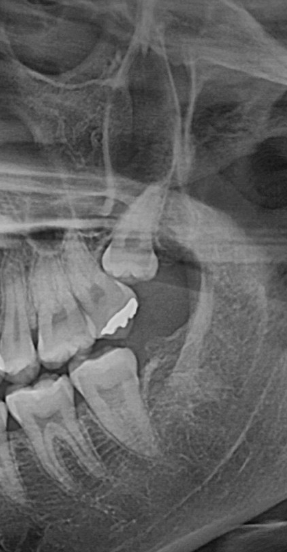

그 이유는 명확합니다. 사랑니는 개인마다 나는 방향, 묻혀 있는 깊이, 뿌리의 형태가 모두 다르며, 이에 따라 발치 난이도가 현저히 달라지기 때문입니다.**

## 사랑니가 난 방향이 난이도를 결정합니다

사랑니가 어느 방향으로 나 있느냐는 발치 난이도에 직접적인 영향을 미치는 핵심 요소입니다.

- 옆으로 누워서 난 경우(수평 매복) → 난이도 증가

- 잇몸깊은 곳을 향해 난 경우 → 고난도 수술

특히 잇몸 방향으로 향한 사랑니는, 치아가 자연적으로 이동하려는 방향 자체가 뼈 안쪽이기 때문에 발치 시 매우 까다로운 술식이 요구됩니다.

첨부 이미지

사랑니 발치, 얼마나 걸릴까? 시간과 비용의 모든 것 - 이미지 2